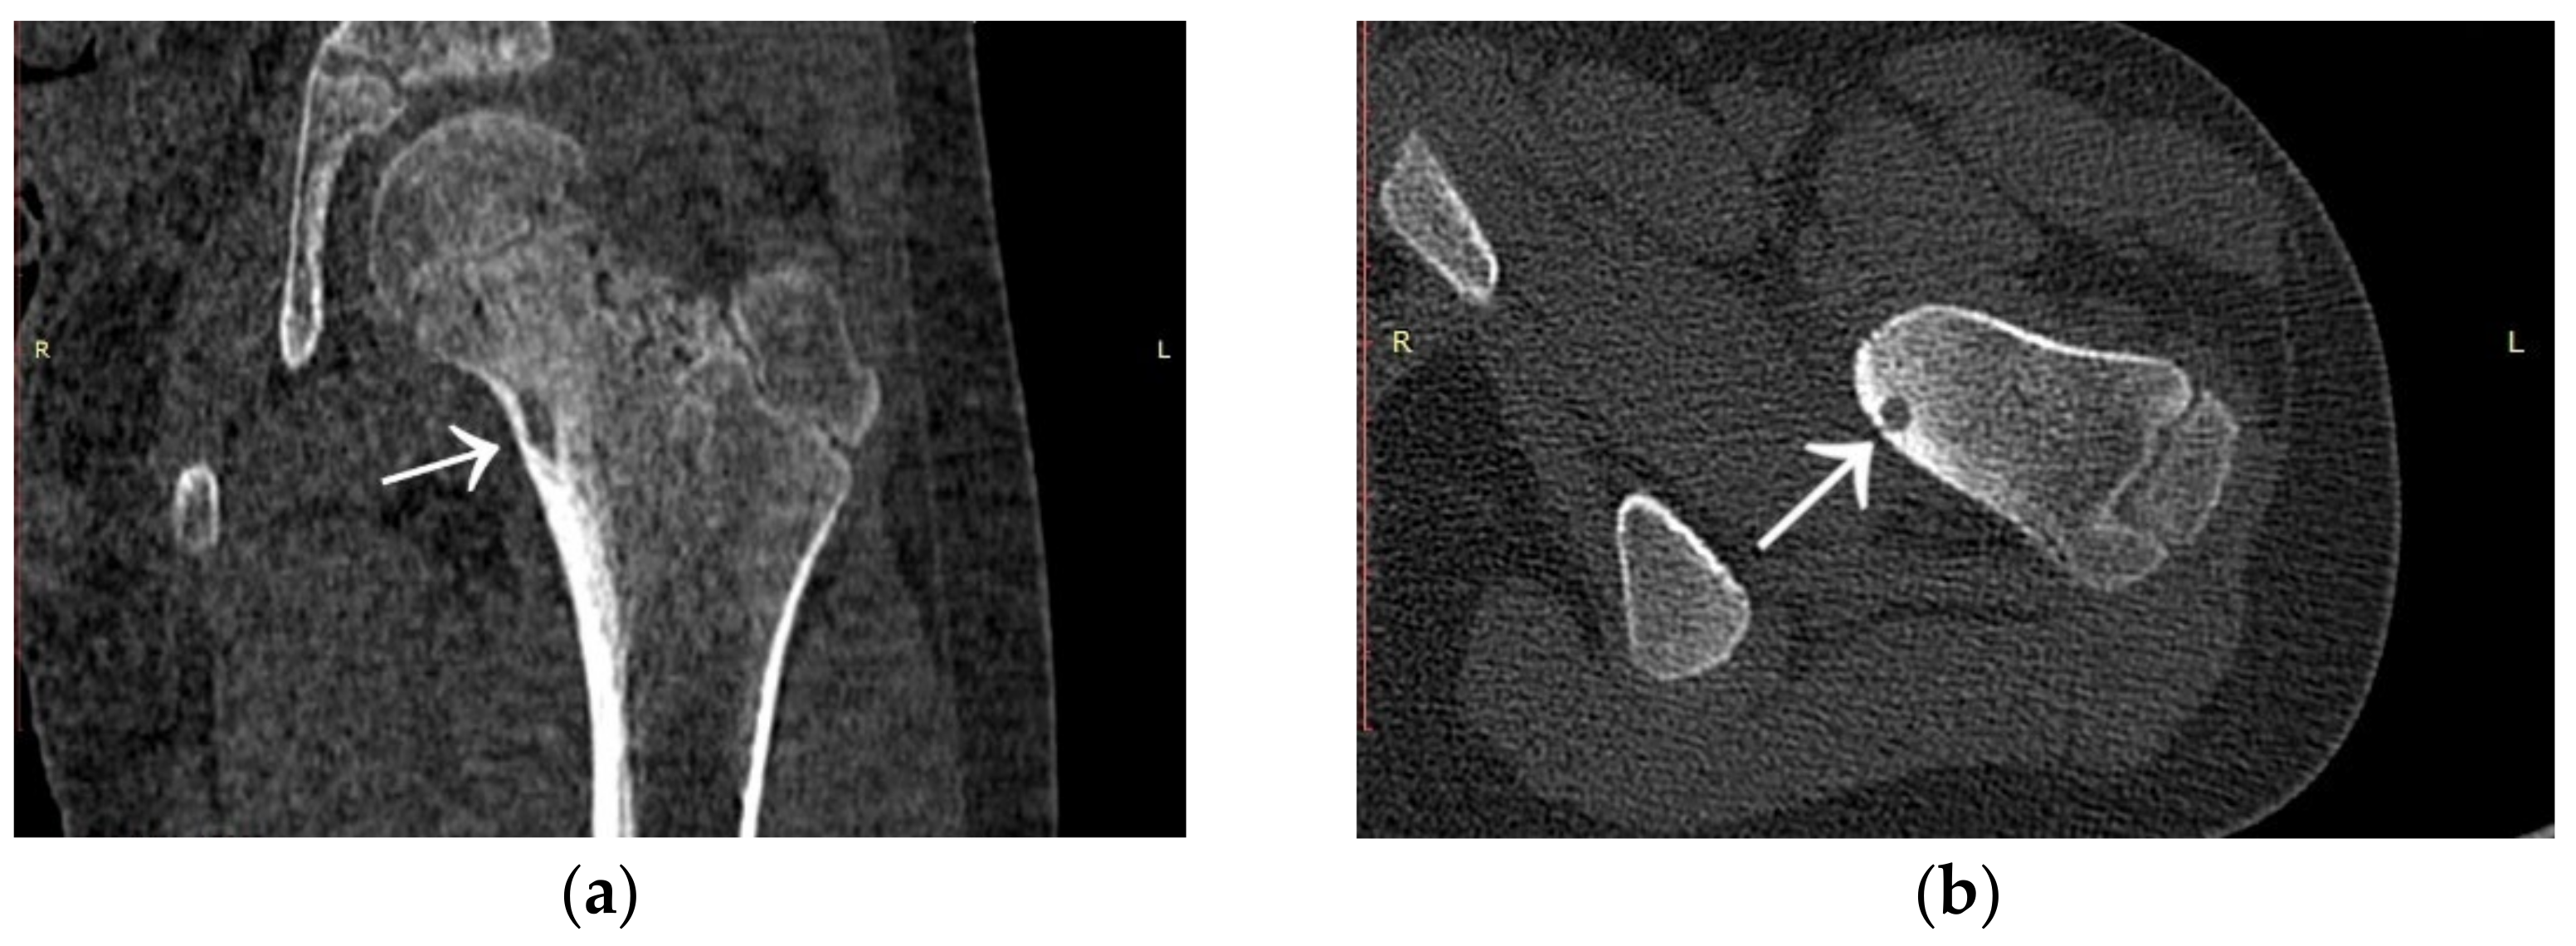

3.2. Case 2: Example of an Incorrect Therapeutic Path of OO

A 35-year-old male patient presented with a diagnosis of inadequately treated osteoid osteoma for two years. The patient informed of pain at night and during the day after exercise or prolonged immobilisation of the limb (sedentary work). The suspicion of OO in the right distal metaphysis of the right femur (a nidus size of 12 × 4 × 4 mm) was raised from the first X-ray examination and a CT scan performed two years earlier. Pain was localised exclusively to the right limb; however, on examination, an incidentaloma was detected in the posterolateral part of the femoral diaphysis on the opposite side with an initial suspicion of a proliferative process. Following an MRI scan of the left knee joint, a suspicion of a non-ossifying fibroma in the healing phase was raised. In a subsequent examination, bone scintigraphy was performed. A focus of pathological tracer accumulation in the right femur was described as a suspected benign lesion, but proliferative disease could not be excluded. After further additional examinations, the patient was qualified for resection of the right femoral tumour. The resection procedure was performed, and the specimen was collected for histopathological examination. After surgery, there was no improvement in terms of pain, and extension contracture of the knee joint (flexion to a level of 120 degrees) developed. The histopathological examination suggested a diagnosis of haemangioma. After further clinical examinations and additional examinations (including a CT scan) (Figure 3), the absence of the features of osteoid osteoma recurrence was described, and pain was associated with the features of a femoropatellar joint injury. Histopathological specimens were re-analysed with the result that there were no features of malignant cells or osteoid osteoma. Over the following months, persistent night pain extending to the anterior surface of the patella and right lower leg was reported. On clinical examination, flexion of the right knee with pain in the medial distal part of the thigh occurred. The subsequent diagnostic process at a rheumatology outpatient clinic suspected gout. The patient was treated with colchicine for several months without any signs of improvement. A second look at the CT scan confirmed a diagnosis of persistent focus of OO. The patient was admitted to the Department of Orthopaedics with muscular atrophy of the right lower limb, impaired mobility (limitation of knee joint flexion of approximately 30 degrees), pain VAS of 6, to perform thermoablation of the lesion resection site. The patient underwent the above procedure under general anaesthesia (Figure 4). On examination the day after surgery, there was a significant reduction in pain (VAS score of 1). On examination 3 months after surgery, there was complete resolution of pain (VAS scope of 0), active flexion of the knee joint without pain, and the patient’s return to activities of daily living. He was recommended to undergo active rehabilitation to restore full limb function.

Figure 3.

CT scans of the right femur showing flat cortical bone (arrows) after attempted resection and persistent focus of OO. (a) Frontal CT scan; (b) Transverse CT scan.